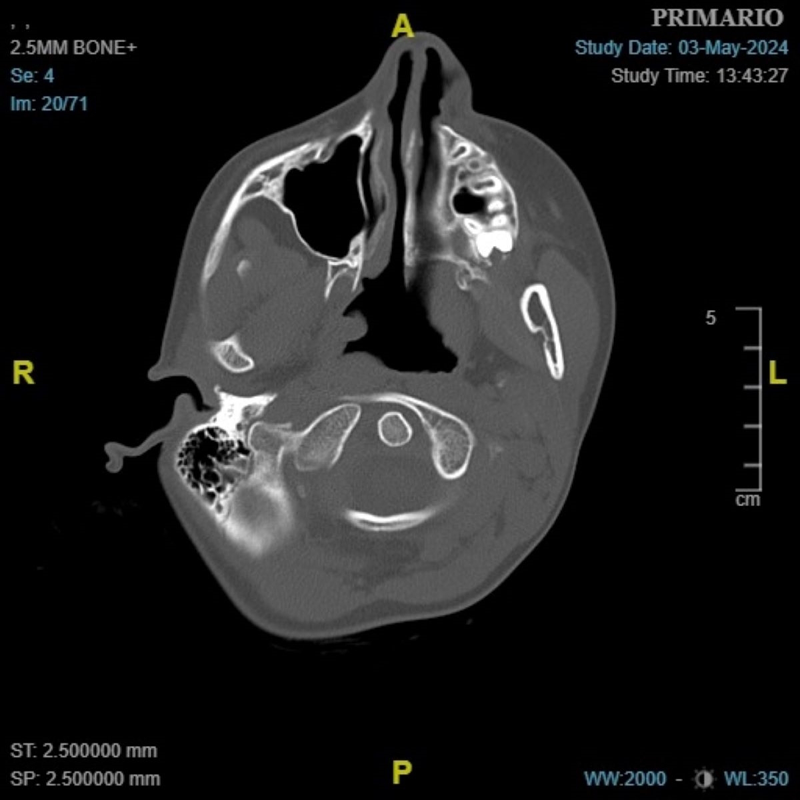

Es­co­lar con tor­tí­co­lis: un e­nig­ma cer­vi­cal

Niña de 9 años de edad, sin antecedentes de interés, que ingresa por cuadro de fiebre, adenitis cervical y tortícolis para la administración de antibioterapia (cefazolina, clindamicina), antiinflamatorios y corticoides i.v. Durante el ingreso presenta desaparición de la fiebre, disminución del tamaño de la adenopatía y mejoría discreta del dolor, pero persiste la tortícolis rígida.